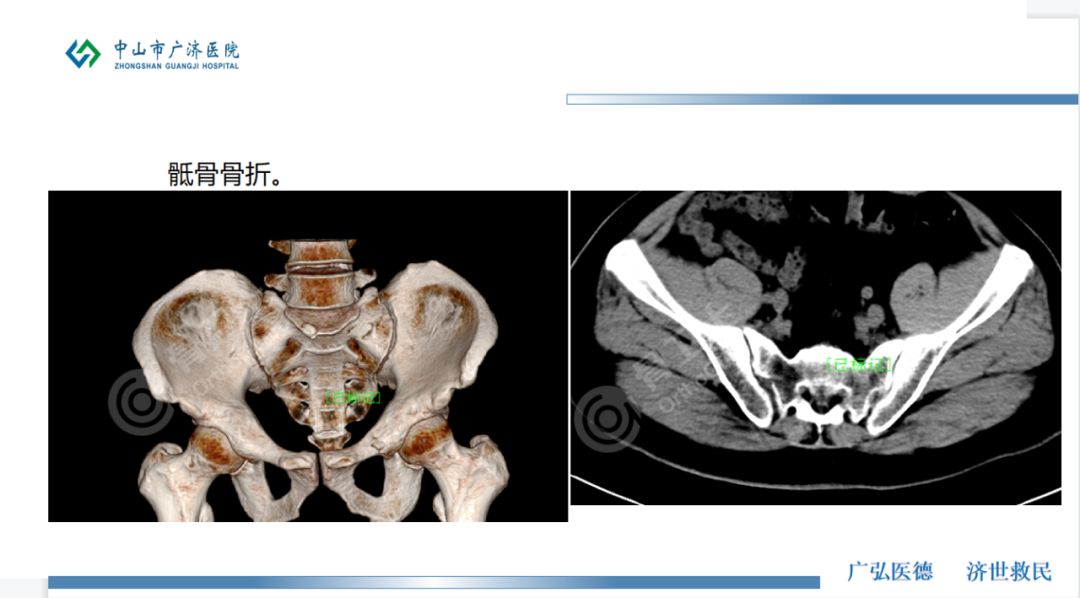

【入院诊断】左尺骨鹰嘴骨折,骶1椎体骨折,左侧骶骨翼多发粉碎性骨折,左肘部皮下血肿,全身多处皮肤软组织挫伤。

▲患者术前影像